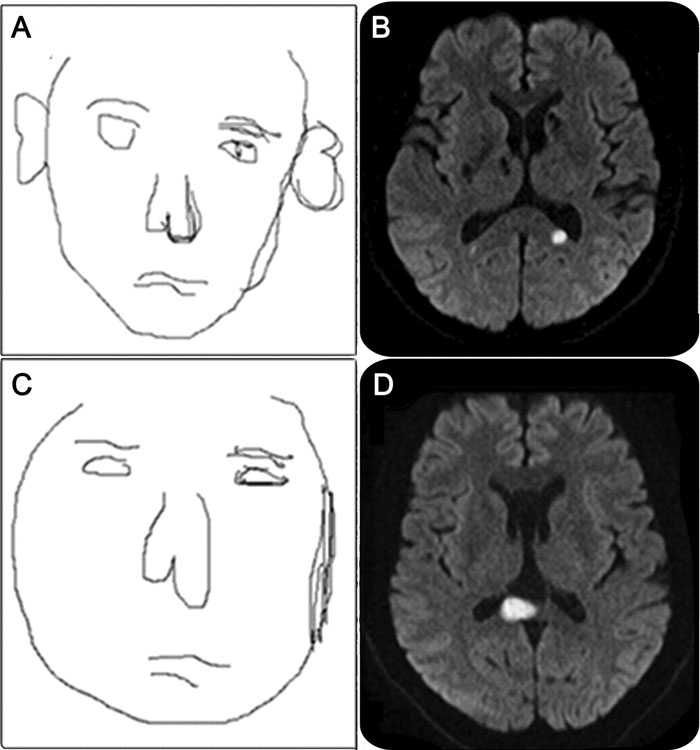

*MRI는 뇌 병변을 발견했는데, 의사는 이것이 색깔과 얼굴을 처리하는 뇌 부분에 영향을 미쳤다고 믿는다.

그러나 그녀의 뇌 MRI에서는 담창구 핵 근처에 여러 병변이 발견되었다. 이 뇌의 부분이 손상되면 기억력과 처리 속도 등의 인지 저하와 관련이 있으며, 정신분열증 및 기타 신경학적 및 정신 질환과 연관되어 있다.

의사들은 MRI에서 드러난 병변이 색상과 얼굴을 처리하는 뇌의 부분인 복측 후두측두피질에서 비정상적인 전기 활동을 유발했을 수 있다고 의심하고 있다.

연구 결과를 고려하여, 그들은 환자를 얼굴 모양, 질감, 위치 또는 색상이 왜곡되어 보이는 매우 드문 신경 장애인 얼굴 변형 환상증(prosopometamorphopsia, PMO)으로 진단했다.

의사들은 그녀의 뇌에 있는 병변이 얼굴을 처리하는 뇌 영역에서 비정상적인 전기 활동을 유발했다고 이론을 세웠다.

10대 때 양극성 장애 진단을 받은 빅터는 인간의 얼굴을 어떻게 인식하는지를 보여주는 컴퓨터 생성 2D 그림을 만들어 PMO 연구에 기여했다.